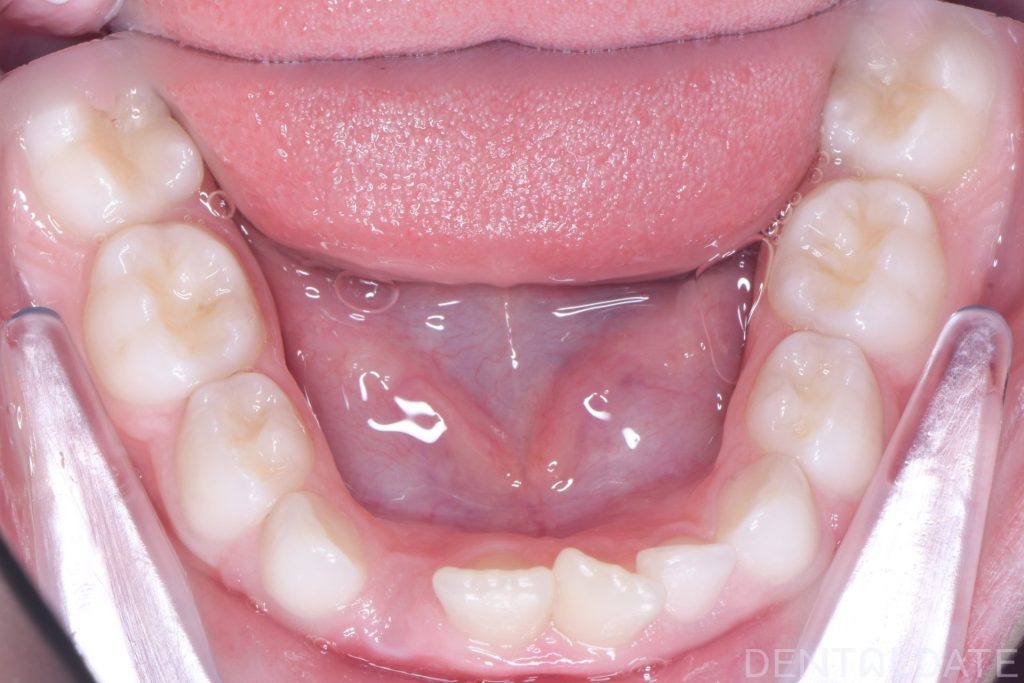

A Haas appliance was placed as the first stage of treatment, followed by the use of a myofunctional appliance.

Because the treatment was initiated right on time, there was no need for 2*4 braces. The child continues to grow and develop normally.